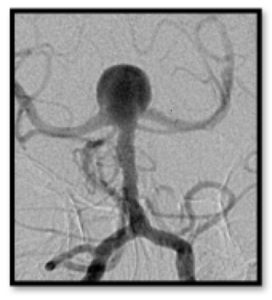

Intracranial aneurysms are unnerving, but not all aneurysms are created equally. It’s no secret that nearly 50% of people with intracranial aneurysm ruptures die before they get to the hospital, and of the 50% who make it to the hospital, about 30% die despite our best efforts. Our office often gets urgent referrals from non-neurosurgical offices for incidentally found aneurysms that were discovered during workups for chief complaints such as dizziness or headache. Not all aneurysms are life threatening, and not all need an immediate referral to the emergency department; some just need monitoring by a provider who treats aneurysms on a regular basis.

One of the more recent studies being discussed in the cerebrovascular care community is out of Japan, The Unruptured Cerebral Aneurysm Study of Japan (UCAS Japan) 2012 (5,720 patients, 6,697 aneurysms). Unlike the ISUIA Phase 2, UCAS authors assessed an annual rupture rate (0.95%) as opposed to a 5-year rate and considered treatment for aneurysms that are ≥5 mm, as opposed to ≥7 mm in ISUIA. In another difference, UCAS authors found that non-smooth aneurysms (those with daughter domes) have a higher rupture rate compared with smooth aneurysms. Lastly, with regard to location, UCAS results show higher risk of rupture in both the ACom and PCom regions, whereas ISUIA identifies higher rupture rates only in the posterior circulation. The downside to this study is its limited generalizability outside of the Japanese population, who have a higher risk for subarachnoid hemorrhage than other populations.

- Aneurysm has an odd, non-smooth morphology (daughter domes)